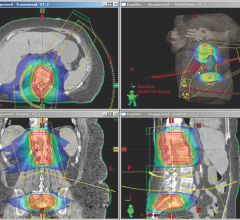

Decatur Memorial Hospital, Decatur, Ill., is now offering C-11 choline positron emission tomography (PET)/computed tomography (CT) and PET/magnetic resonance imaging (MRI) to patients who have biochemical relapse of prostate cancer. This comes after completing a two-year clinical trial to detect prostate cancer in earlier stages.